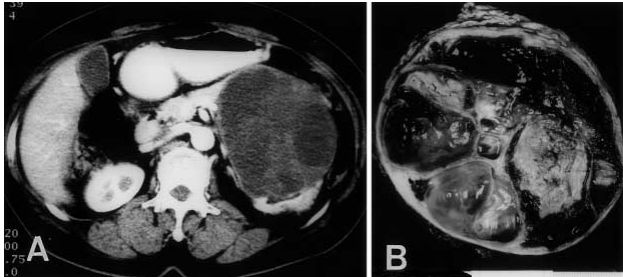

一名 63 岁,既往健康的女性,有 6 个月的上腹部不适病史。所有实验室资料均正常,包括肿瘤标志物。腹部 CT 显示在胰腺尾部有一个 10 cm 的多囊性肿块(图 3.1A),怀疑是胰腺的囊性肿瘤 。

图 3.1 CT 扫描 (A) 和肿块 (B) 的切面 CT 扫描显示在胰腺的尾部有一个 10 厘米的多囊性肿块。肿瘤边界清楚,被厚纤维组织和正常胰腺实质覆盖。有广泛的囊肿形成和出血。